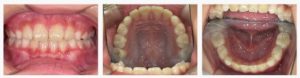

▼After(治療後)

治療を進めるうちに、舌の位置と呼吸の仕方が安定し、あごの幅が自然に広がってきました。

その結果、前歯の重なりが軽減し、歯列がきれいなアーチ状に整いました。